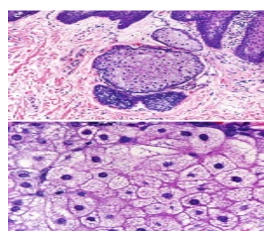

Upon microscopic examination, mature sebaceous glands appear aggregated subjacent to mucosal epithelium. The visible sebaceous glands appear in continuum with superimposed cutaneous surface and are devoid of associated hair follicles [6,7]. Nevertheless, a ductal communication with superficial epidermis may be absent [6,7].

The morphological countenance is akin to normal cutaneous adnexal sebaceous glands. Superimposed stratified squamous epithelium demonstrates parakeratosis and exhibits subjacent lobules of mature sebaceous glands [6,7].

Figure 4: Fordyce's granules exemplifying numerous sebaceous lobules incorporated with lipids and an enveloping acanthotic stratified squamous epithelium (12).

Figure 5: Fordyce's granules exhibiting enlarged sebaceous glands with lipid laden lobules and a superficial hyperkeratotic epidermal layer (13).